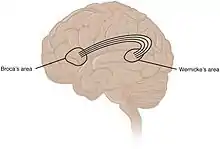

While language functions were traditionally thought to be localised to Wernicke's area and Broca's area,[102] it is now mostly accepted that a wider network of cortical regions contributes to language functions.[103][104][105]

Paul Broca associated regions of the brain with specific functions, in particular language in Broca's area, following work on brain-damaged patients.[250] John Hughlings Jackson described the function of the motor cortex by watching the progression of epileptic seizures through the body. Carl Wernicke described a region associated with language comprehension and production. Korbinian Brodmann divided regions of the brain based on the appearance of cells.[250] By 1950, Sherrington, Papez, and MacLean had identified many of the brainstem and limbic system functions.[251][252] The capacity of the brain to re-organise and change with age, and a recognised critical development period, were attributed to neuroplasticity, pioneered by Margaret Kennard, who experimented on monkeys during the 1930-40s.[253]